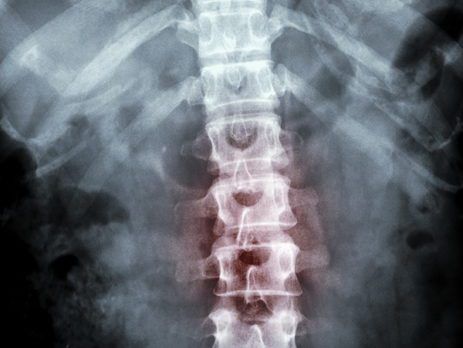

THE PATH TO DIANOSIS: LOWER BACK PAIN

Understanding Range of Motion in the Lumbar Spine The most-reported pains and strains are in the lower back region. Pain typically begins as dull and aching and progresses to significant over time. Lower back pain can alter the very essence of how you usually function and should not be ignored. [...]